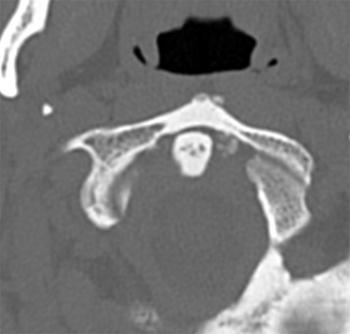

Le scanner cervical montrait un nuage autour de l'odontoïde (cliché), ce qui a permis le diagnostic de rhumatisme à hydroxyapatite et dans ce cas particulier, un syndrome de la dent couronnée.

De nombreux diagnostics ont été proposés par nos lecteurs : spondylodiscite, dissection artérielle, abcès paravertébral, diagnostics qui ne tenaient pas compte de